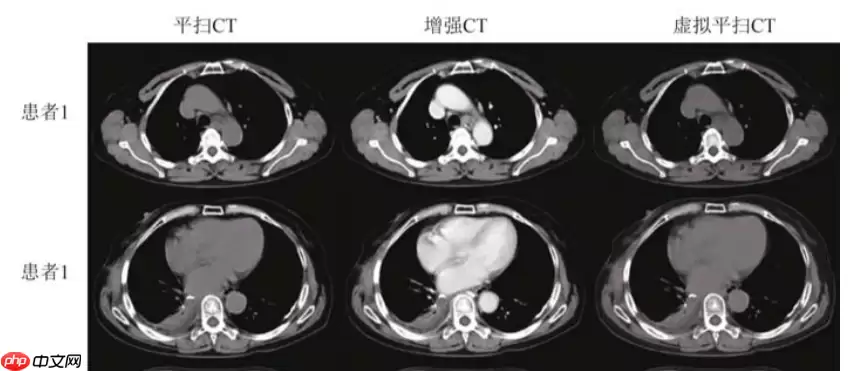

[1]高留刚, 李春迎, 陆正大,等. 基于卷积神经网络生成虚拟平扫CT图像[J]. 中国医学影像技术, 2024, 38(3):5.

【1】文章使用Unet对增强CT数据进行训练,最终预测生成对应的虚拟平扫CT图像,达到只需要对患者扫描一次CT即可,避免患者接受过多的放射辐射。